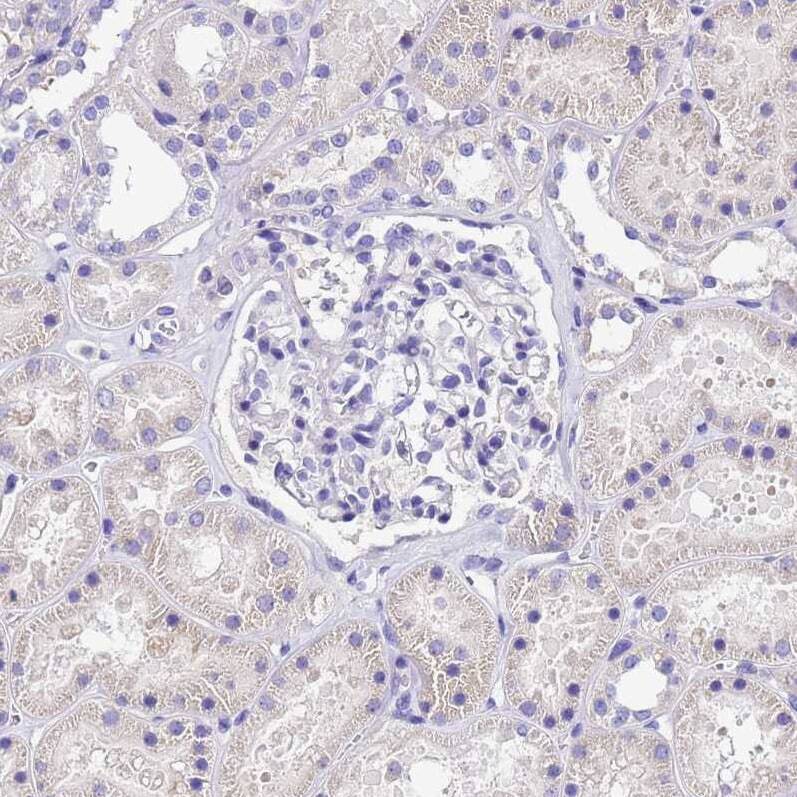

- Immunohistochemical analysis of UD2A1 in human kidney using UD2A1 Polyclonal Antibody (Product # PA5-53569) shows weak cytoplasmic positivity in cells in tubules.